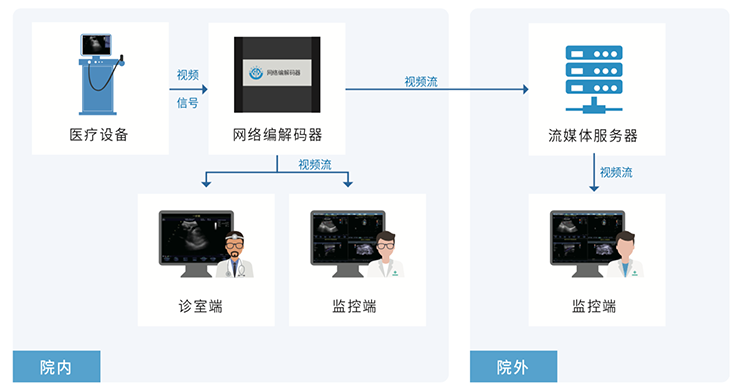

- 多画面实时监控,音视频交流。

- 基于互联网通信方式。

院内实时监控系统